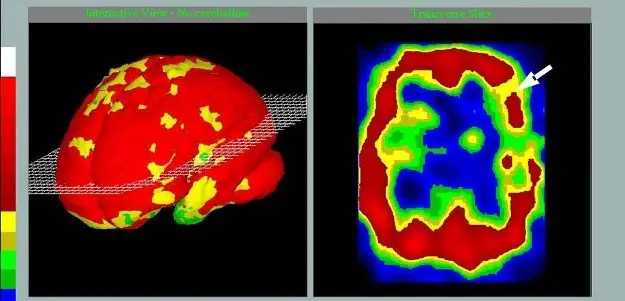

У него не развился типичный ишемический инсульт с некрозом участка мозга, как это обычно бывает при сочетанной патологии сердца и критическом сужении мозговых сосудов. Есть такое понятие в диагностике мозгового кровотока — «снижение резерва компенсации мозгового кровотока». Как показало обследование, у него этот резерв был критически снижен. — «снижение резерва компенсации мозгового кровотока».

Мы использовали разработанные нами крайне эффективные методы оценки кровообращения головного мозга. Мы использовали разработанный нами атеросклеротический тест. Исследовали кровоток головного мозга, учли ключевые физические параметры движения крови по сосудам. И что важно, мы провели расчет степени компенсации кровотока мозга и определили, за счет каких сосудистых бассейнов (артериальных и венозных) можно данный резерв компенсации. Такие исследования дали возможность выстроить оптимальную лечебную тактику по оптимизации кровотока головного мозга. Сделал свой вклад и кардиолог клиники. Поскольку атеросклероз – это не только поражение мозга, но многих сосудов, включая сосуды сердца.

Были диагностированы не только атеросклероз, но и критическое снижение скоростных показателей крови в сосудах мозга. Причем стали известны конкретные сосудистые бассейны, в которых кровоток был снижен критично. Более того, были выявлены причины атеросклероза. Не говоря уже о сопутствующей патологии, которые также могли привести к фатальному концу.